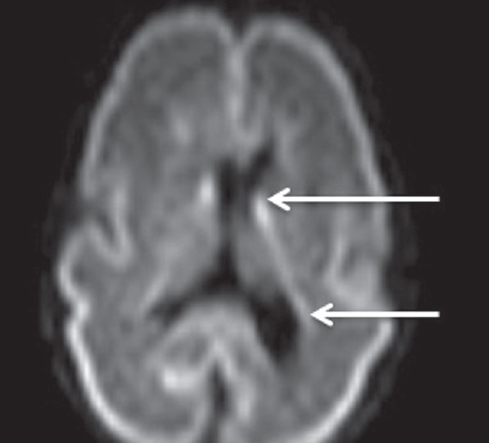

In MRI studies on premature infants at PCAs of 27–32 weeks, the germinal matrix was visualized in eight premature infants as DWI–MRI signals along the side walls of the brain lateral ventricles, as well as along the anterior horns above the caudate nuclei on both sides (Fig. 4). The germinal matrix was reliably detected in T2-weighted images from seven neonates (Fig. 5) and in T1-weighted images from two neonates (Fig. 6). The germinal matrix could not be visualized using FLAIR sequences.

Fig. 5. MRI of preterm newborn (PCA 28 weeks), Т2-WI, axial plane. Arrows mark the areas of the germinal matrix located along the external walls of the lateral ventricles (hypointense MR signal)

Рис. 5. МРТ головного мозга недоношенного ребенка (ПКВ 28 недель). Т2 ВИ, аксиальная проекция, стрелками выделены участки

In the present study, the germinal matrix could be visualized using the T1-pulse sequence in only two infants at PCAs up to 32 weeks, as a hyperintensive signal from the lower wall of the anterior lateral ventricles. Using the T2-pulse sequence, the germinal matrix was detected in seven out of nine infants at PCAs of 27–32 weeks, as a hypointensive MRI signal from the anterior sections and outer walls of the lateral ventricles. S. Counsell recommends using a T2-pulse sequence to measure cerebral maturity in premature infants [4]. S. Counsell reported a decrease in the intensity of the T2 signal from the lateral walls and anterior sections of the lateral ventricles in premature infants at PCAs of up to 32 weeks. As suggested by S.J. Counsell, the preservation of the hypointense T2 signal from these structures in premature infants with PCAs above 32 weeks may indicate a glial migration disorder [5].